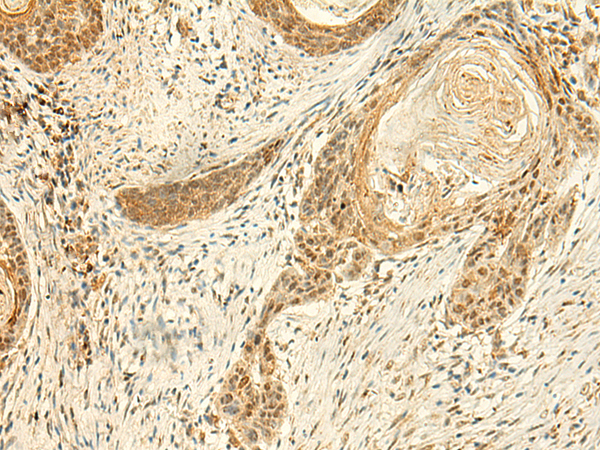

分类: 科研抗体货号: P10060别名: GST; GST13; hGSTK1; GSTK1-1; GST13-13; GST 13-13应用: WB,IHC反应种属: Human